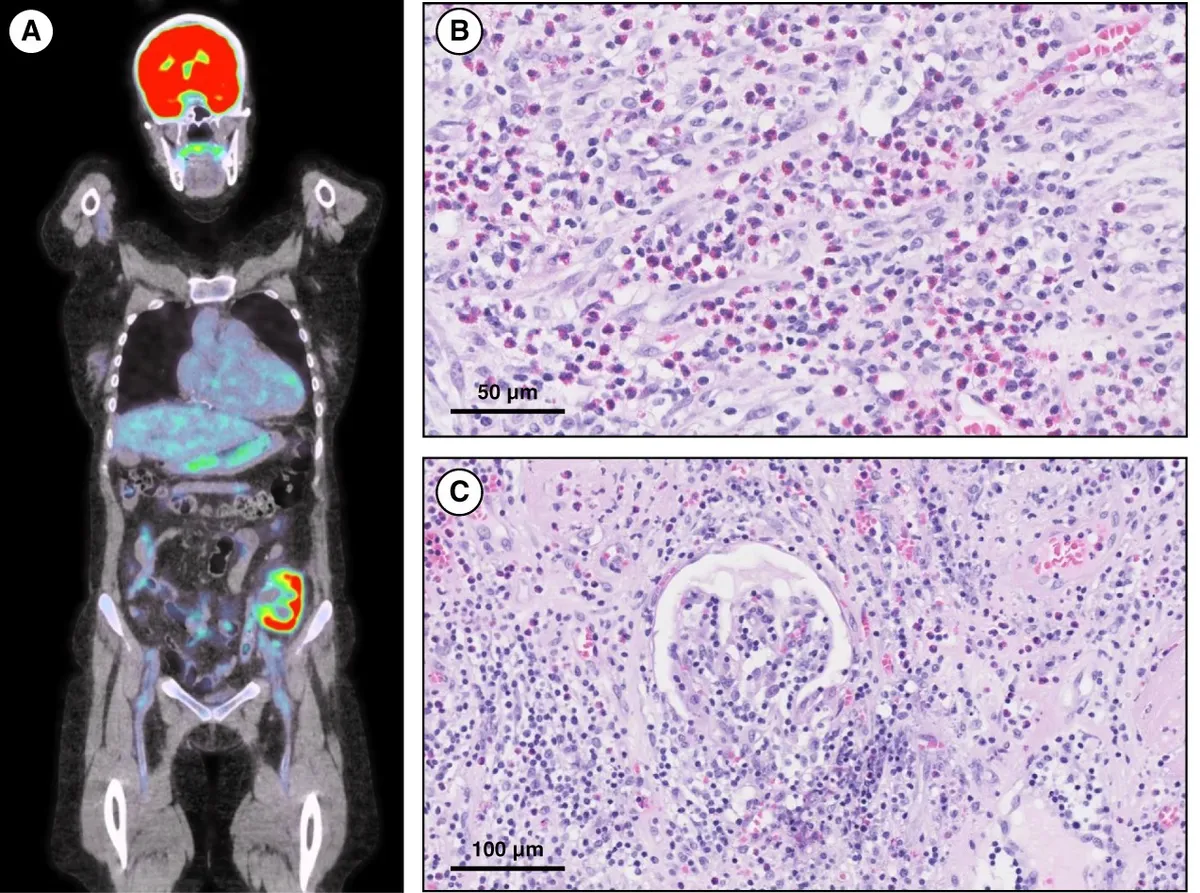

IRA + Icterícia: Um Caso que Exige Investigação Detalhada

IRA + Icterícia: Um Caso que Exige Investigação Detalhada